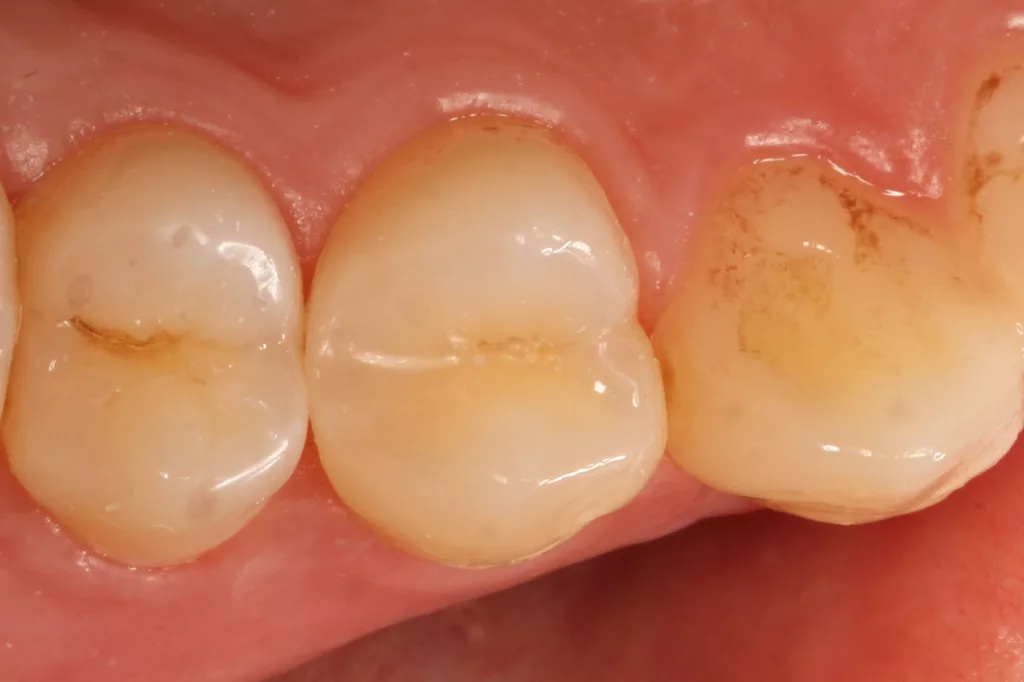

Fall 2: Versorgung einer Initialkaries an Zahn 14 und später an 15

Die 26 Jahre alte Patientin störte sich an der approximalen Lücke zwischen den Zähnen 14 und 15, da sich hier ständig Speisereste impaktierten. Bei der klinischen Inspektion fiel die Initialkaries distal an Zahn 14 auf (Abb. 7). Die Patientin wurde dahingehend beraten, den Spalt mit einer minimalinvasiven Kompositrestauration zu versorgen – bei zeitgleicher Exkavation der Karies an Zahn 14. Nach Exkavation und Präparation des Defektes (der sich als deutlich ausgeprägter präsentierte als anfangs angenommen) erfolgte identisch zu Fall 2 die Ausformung der Kavität mit einer Teilmatrize (Danville ultra thin flex), einem Kunststoffkeilchen (G-Wedge) und der Separation mit einem NiTin-Prämolaren-Spannring (re-invent, Abb. 8).